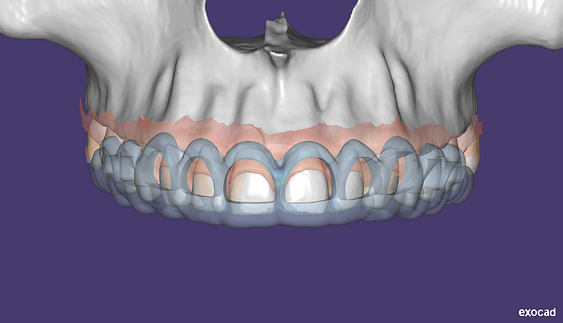

This is one feature that actually made Diagnocat very popular early on. It was the only software that made CBCT segmentation easy. Nowadays, there are several different companies and software that carry out segmentation. Diagnocat was the first and is still arguably the best at it.

So what is Segmentation? It basically means taking the CBCT and delineating all the different 3D structures, bones, individual teeth, etc.

These can then be individually exported via the software by generating STL files from CBCT dicom data. This can be used in other dental software. Jaw STLs can be used in Modjaw (jaw motion capture) for TMJ analysis, for example. As well as in exocad to help visualize the jaws for surgical planning or guide creation.

Being able to take a DICOM file and turn it into STLs is useful for a host of different CAD/CAM indications.

- CBCT segmentation

STLs of upper and lower jaws imported into Modjaw for TMJ analysis in jaw motion. this is made possible by CBCT segmentation using Diagnocat.

The surgical crown lengthening guide was made with the aid of maxilla STL to visualize crestal bone level. Again thanks to CBCT segmentation by Diagnocat.

CBCT Segmentation into STL

Generate STL files from CBCT DICOM data.

Generate maxilla and mandible in one STL file or face, teeth, maxilla, mandible, airway, cranial base, canals as separate STL files.